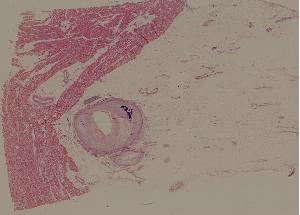

42. Rheumatic pancarditis